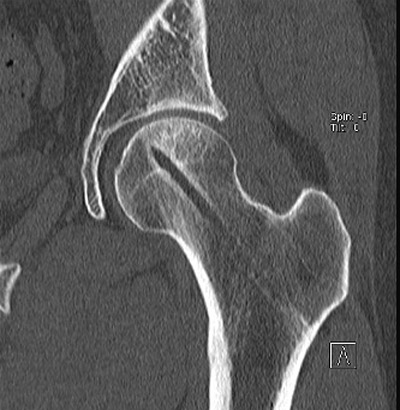

Мы применяем Bone Marrow Aspirate для Pre-collapse состояний. Метод включает аспирацию костного мозга из крыла, центрифугирование, и после разделения на фракции - иньекция через 3 мм инструментом, разработанным компанией BioCUE BIOMET Biologics. Treatment of osteonecrosis with autologous bone marrow grafting. Hernigou P, Beaujean F.

До и через год после лечения.